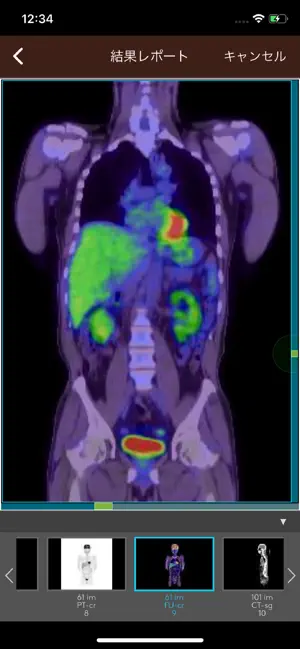

また、ご自身の受診結果についてもアプリ上で閲覧いただけるようになり、受診回数を重ねることで経年変化を確認いただけます。

・結果レポート:ご自身の受診結果内容(数値、画像)をご確認いただけます

※結果レポートの閲覧は2019/4/1以降に受診開始されたものが対象です(一部特例対応があります)。また、結果レポートの閲覧には別途発行いたします「結果レポート認証コード」の登録が必要です